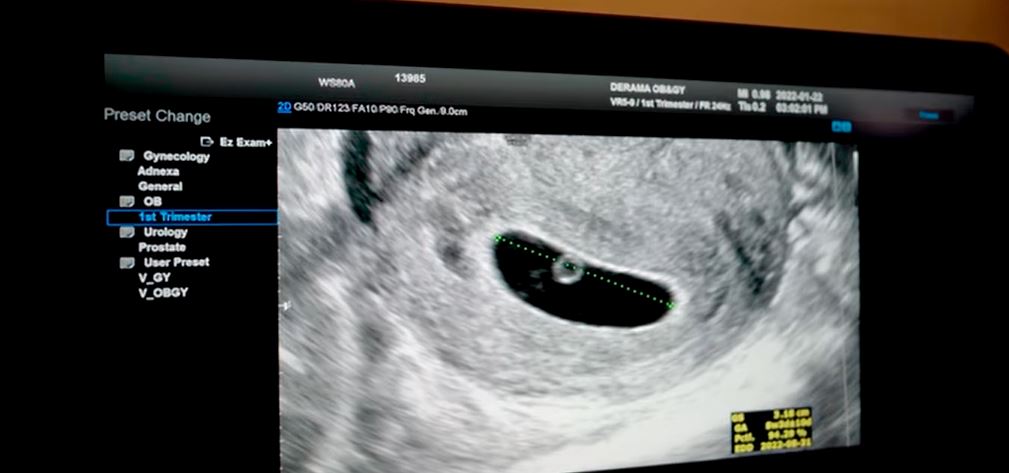

5歲女兒JamJam就非常雀躍開心說:「有了弟弟/妹妹,感覺會比一個人玩更加有趣。以前幼兒園的朋友們每次提到弟弟妹妹時都很羨慕。」然後JamJam陪著媽咪去產檢,拍下胎兒超聲波片段。

照超聲波。